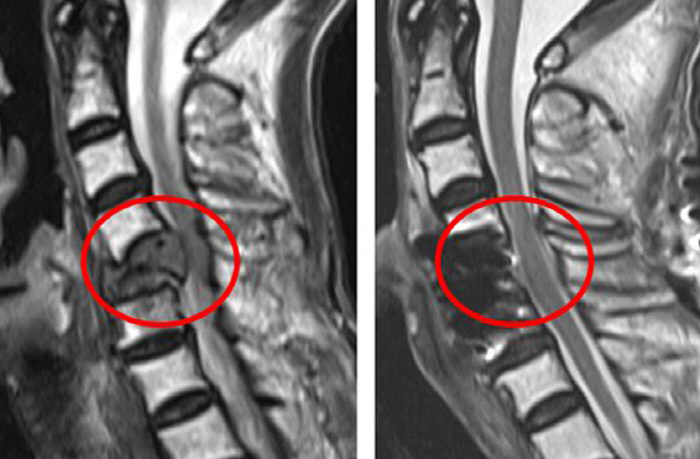

정형외과 수술의 합병증 분류 시스템을 적용하고 다변량 분석결과, 보행 기능의 개선은 수술 전 장요근 지수(PMI, psoas muscle index)와, 수술 후 합병증 발생은 수술 전 영양 상태와 유의한 연관성을 보였다. 장요근 지수는 영상검사로 근육량의 감소를 객관적으로 측정하는 평가인데, 암환자의 근감소증은 수술 후 예후에 좋지 않은 것으로 알려져 있다.

최근 암 치료 기술의 발전으로 암 환자의 생존율도 높아지면서, 암 치료 후 삶의 질을 높이려는 연구도 활발히 진행되고 있다. 암 환자의 70%는 척추 전이를 경험하는데, 과거에는 척추 전이암이 말기라 생각하고 심한 통증에도 치료를 포기하는 경우가 많았다. 하지만 효과적인 표적 항암제 도입 등 치료 기술이 발달했고, 척추 전이암이 진행되면 환자의 거동이 어려워지고 생존율 저하로 이어지기 때문에 적극적 치료가 고려된다.